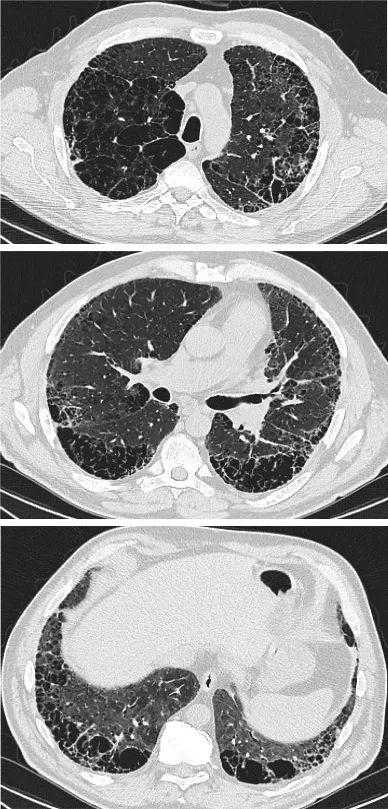

肺气肿是指CT上不以可见壁为界的低密度区[139]。可分为小叶中央型、间隔旁型或全腺泡型[140]。间质纤维化被认为是实质衰减增加的区域,表现为网状影和/或磨玻璃样阴影,以及不同程度地蜂窝状和/或牵拉性支气管扩张(表5)。HRCT上CPFE的肺气肿模式初步被分为不同的组[129,141-143](图1-8);然而,为了更好地定义CPFE的影像学亚型,还需要更多的工作。没有研究正式比较CPFE和COPD的肺气肿模式[140]。

图1:HRCT显示合并肺纤维化和肺气肿的典型疾病分布(单独的肺气肿和纤维化模式)。间隔旁和小叶中央肺气肿局限于上肺,以牵拉性支气管扩张为特征的纤维化局限于下肺。

图2:HRCT显示合并肺纤维化和肺气肿的典型疾病分布(进行性转变模式)。一例72岁特发性肺纤维化患者,主要表现为肺上叶小叶中央型肺气肿,并向肺中部扩散。下肺未见肺气肿。这些表现符合肺纤维化和肺气肿合并的进行性过渡模式。